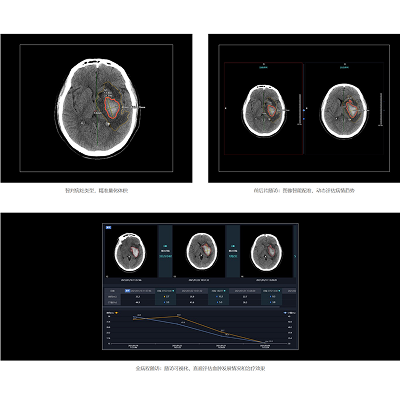

病例展示

一位61岁的男性患者因持续的头晕、头痛症状入院。而其头颅CT影像中一个微小的病灶却让当值阅片医生一时难以判断是出血还是钙化。如果将轻微出血误判为钙化灶,将极有可能导致患者病情延误,后果不堪设想。通过联影智能CT颅内出血智能分析与随访系统对患者图像进行深入分析,AI鉴别出这是脑内的出血情况,同时将其与CT影像图中微小的、易混淆的钙化灶进行了区分。这一准确的诊断为医生提供了重要的参考,他们紧急采取了针对出血的救治方法,避免了误诊和延误。